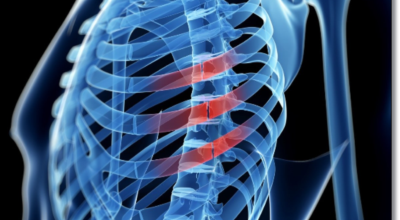

10. 갈비뼈 금간 증상 - 허리 통증

허리 통증도 나타납니다. 갈비뼈에서 나타나는 통증은 흔하게 갈비뼈 부근을 넘어서 허리까지도 통증이 퍼지게 됩니다. 옆구리가 뜨끔하는 통증이 나타나기도 해요.